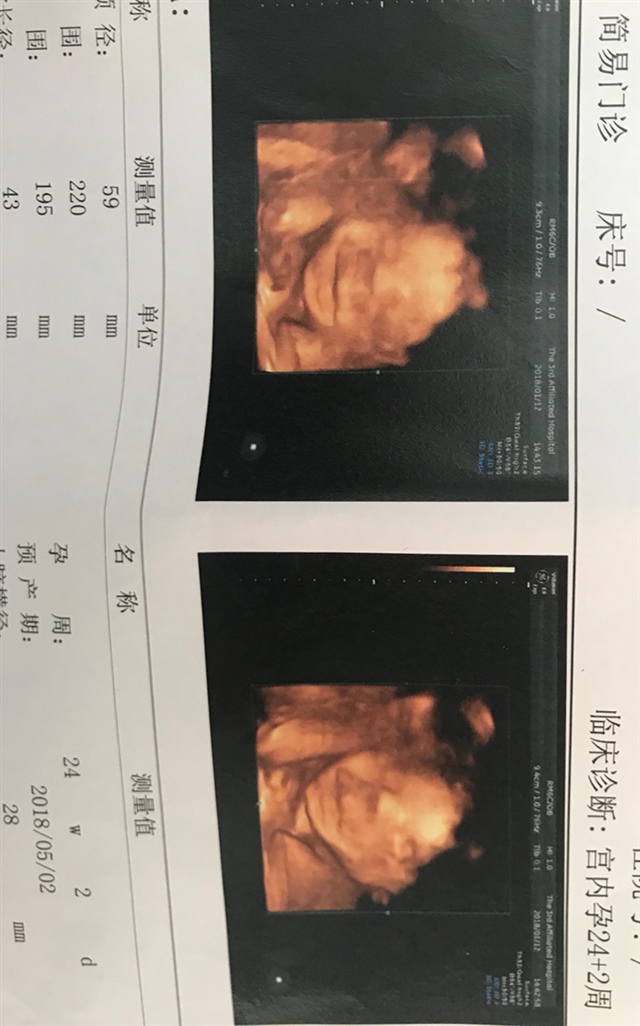

grace[帖主]:24周 2

grace[帖主]:感觉长得有点丑,不过看着他第一张在笑,就忍不住好喜欢😄